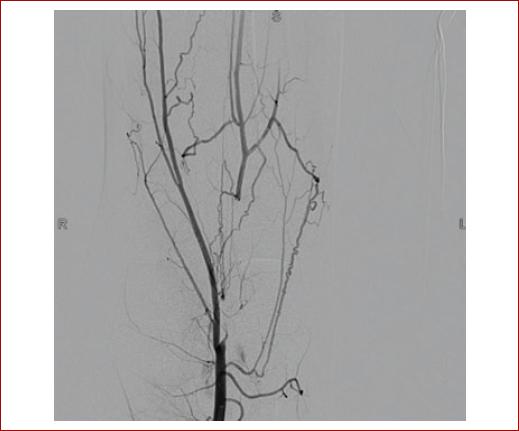

En la sala de hemodinamia, se realiza acceso ecoguiado anterógrado femoral común. La angiografía diagnóstica corrobora oclusión total crónica de la arteria poplítea en su segunda y tercera porciones (P2, P3) (Fig. 2), y de tres vasos tibiales, sin identificar adecuados vasos de salida (Fig. 3). Adicionalmente, se documentan colaterales «en tirabuzón», características (aunque no patognomónicas) de esta patología.

Figura 2 Oclusión completa de la arteria poplítea, P2 y P3. Colaterales «en tirabuzón». No se identifican los orígenes de las arterias tibiales.